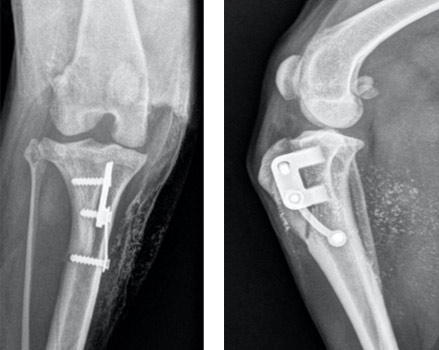

Röntgenbilder des Kniegelenkes eines Appenzellers nach Korrektur einer Patellaluxation 3. Grades.

Die Erholungsphase nach der Operation dauert vier bis sechs Wochen. Meistens wird für ein paar Tage ein Verband angelegt und es werden Schmerzmittel und Knorpelschutz-Präparate verabreicht. Physiotherapie ist sehr zu empfehlen. Nach Entfernen der Häfte wird zudem zu Schwimmtraining geraten.

Vier bis sechs Wochen nach der Operation wird ein Kontroll-Röntgen angefertigt, um den Sitz der Implantate zu prüfen sowie möglichen Komplikationen früh entgegenwirken zu können.